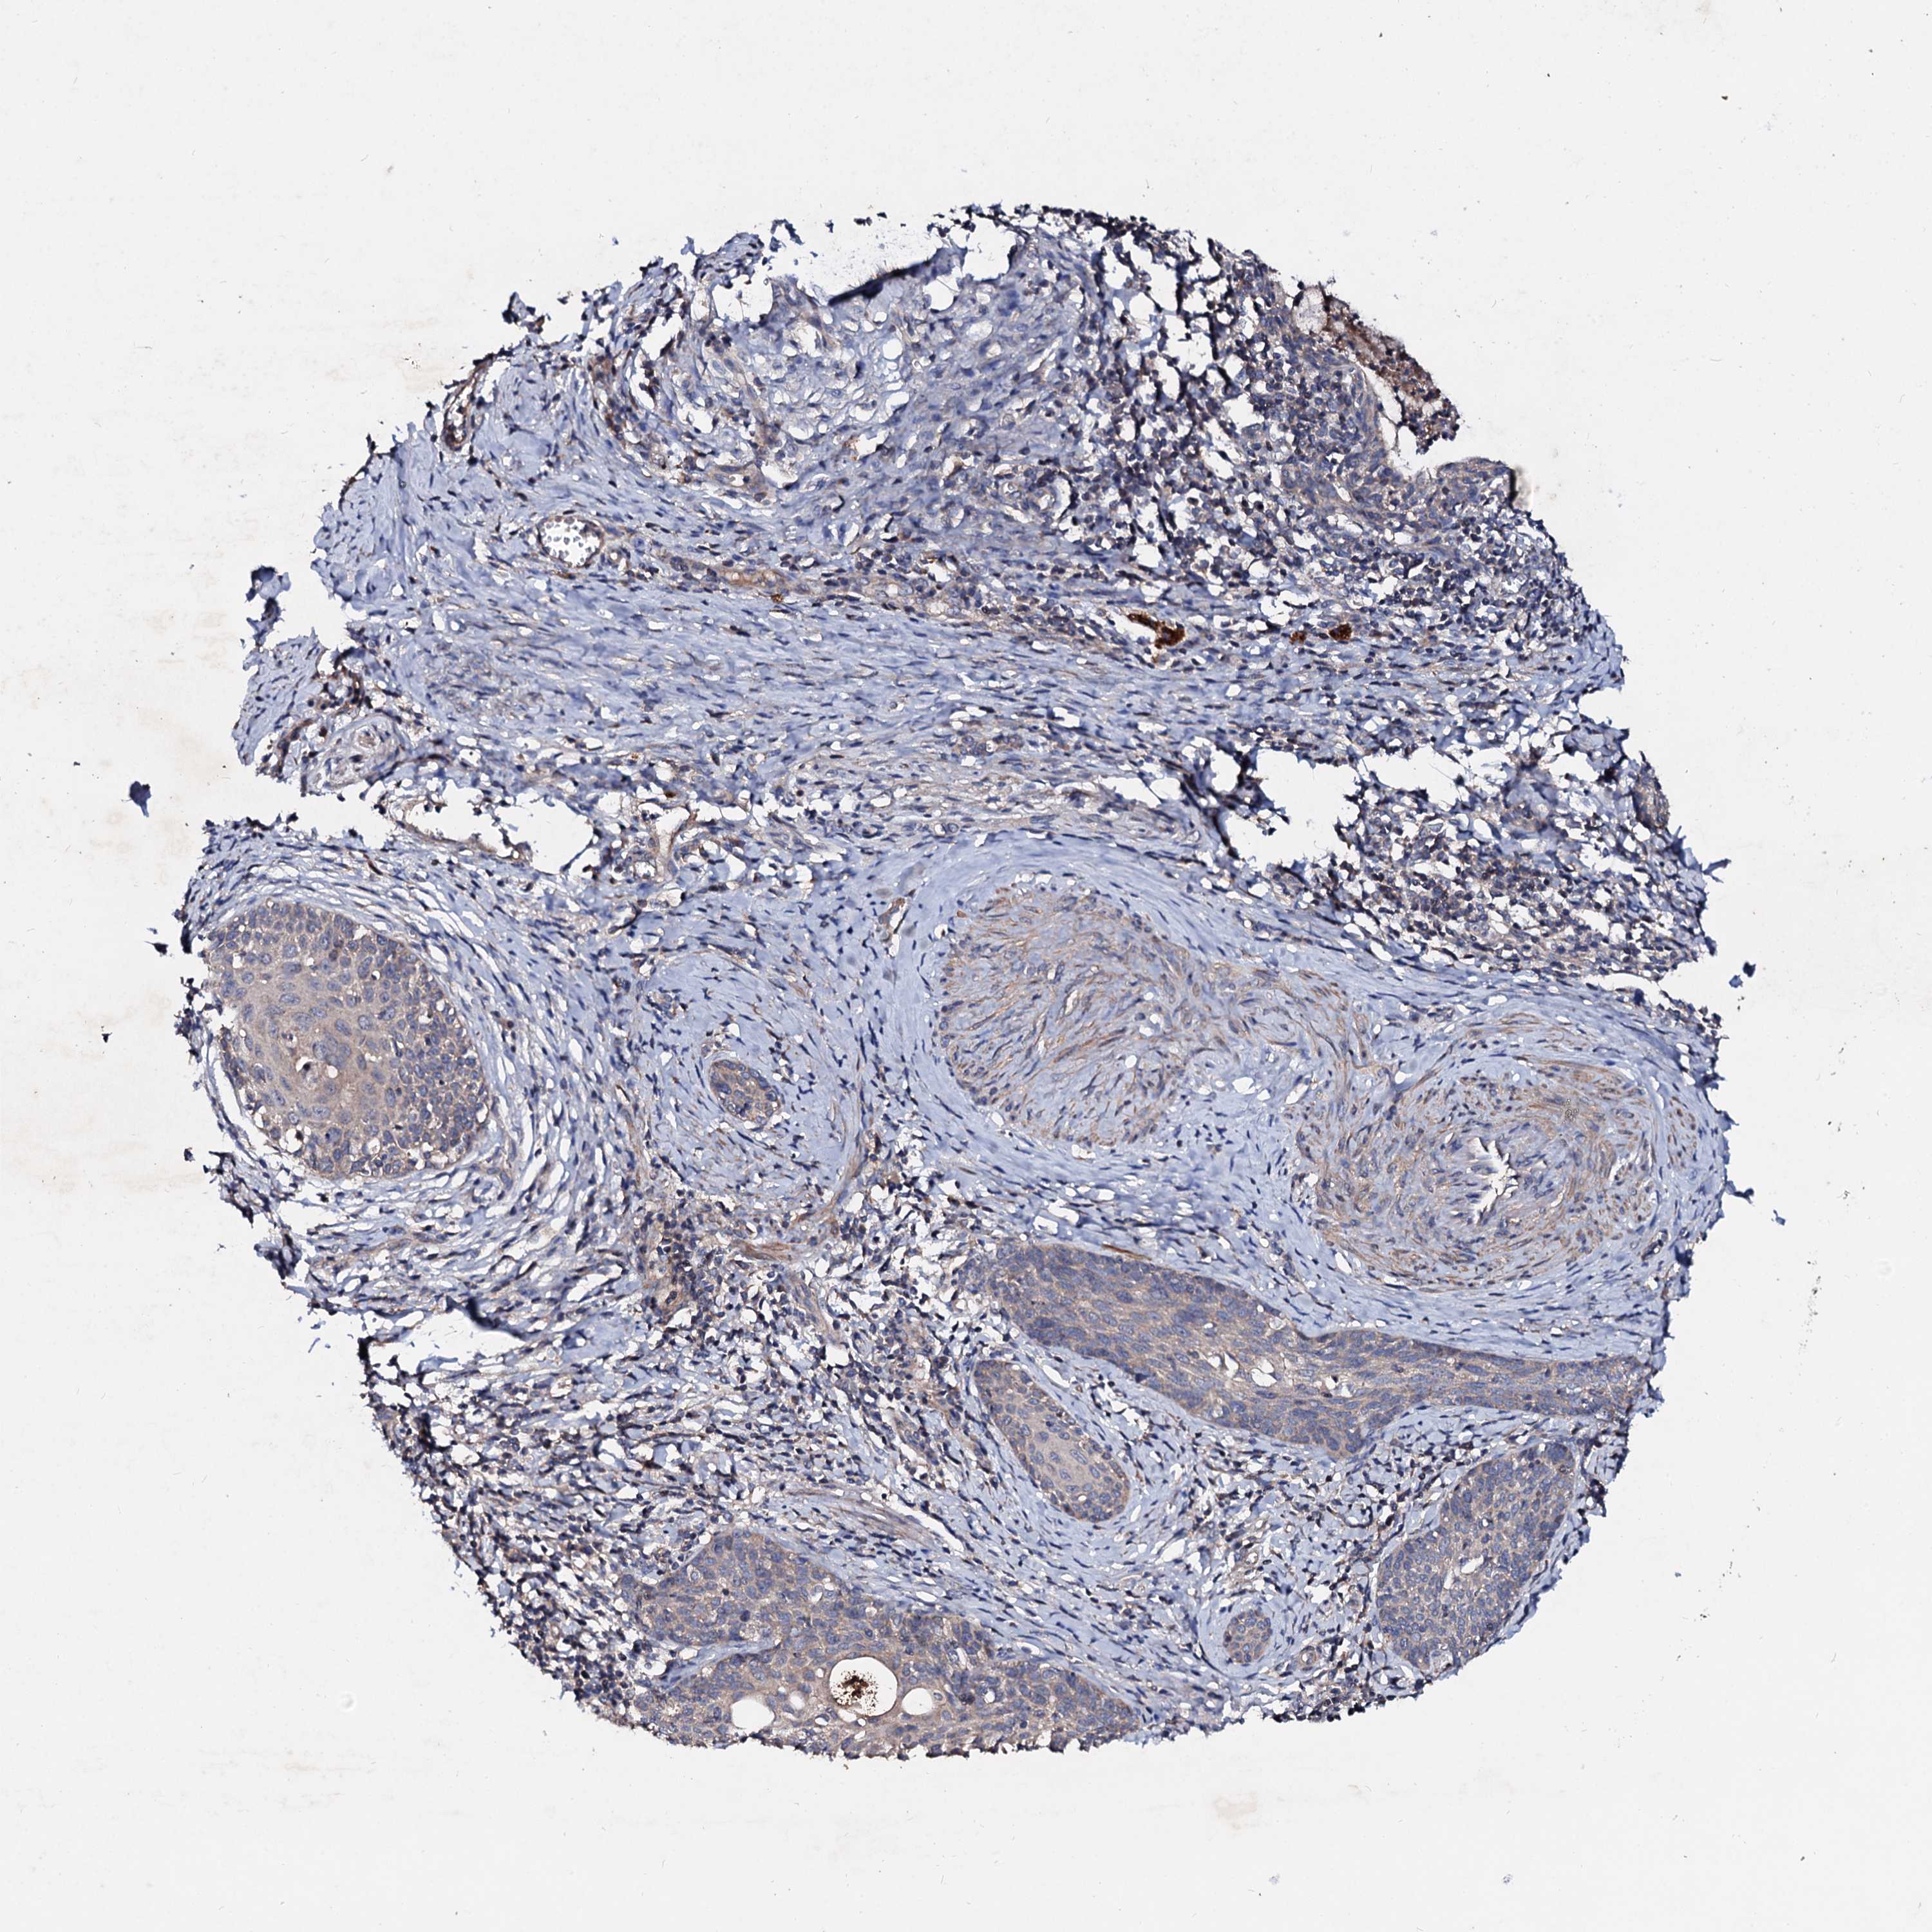

CERVICAL CANCER - Protein expressioni

A mouse-over function shows sample information and annotation data. Click on an image to view it in a full screen mode. Samples can be filtered based on level of antibody staining by selecting one or several of the following categories: high, medium, low and not detected. The assay and annotation is described here.

Note that samples used for immunohistochemistry by the Human Protein Atlas do not correspond to samples in the TCGA dataset.

Antibody stainingi

Antibody staining in the annotated cell types in the current human tissue is reported as not detected, low, medium, or high, based on conventional immunohistochemistry profiling in selected tissues. This score is based on the combination of the staining intensity and fraction of stained cells.

Each image is clickable and will lead to virtual microscopy that enables deeper exploration of all samples and also displays staining intensity scores, fraction scores and subcellular localization as well as patient and tissue information for each sample.

Antibody HPA040120

Staining

High

Medium

Low

Not detected

Intensity

Strong

Moderate

Weak

Negative

Quantity

>75%

75%-25%

<25%

None

Location

Nuclear

Cytoplasmic/membranous

Cytoplasmic/membranous,nuclear

Adenocarcinoma, NOS